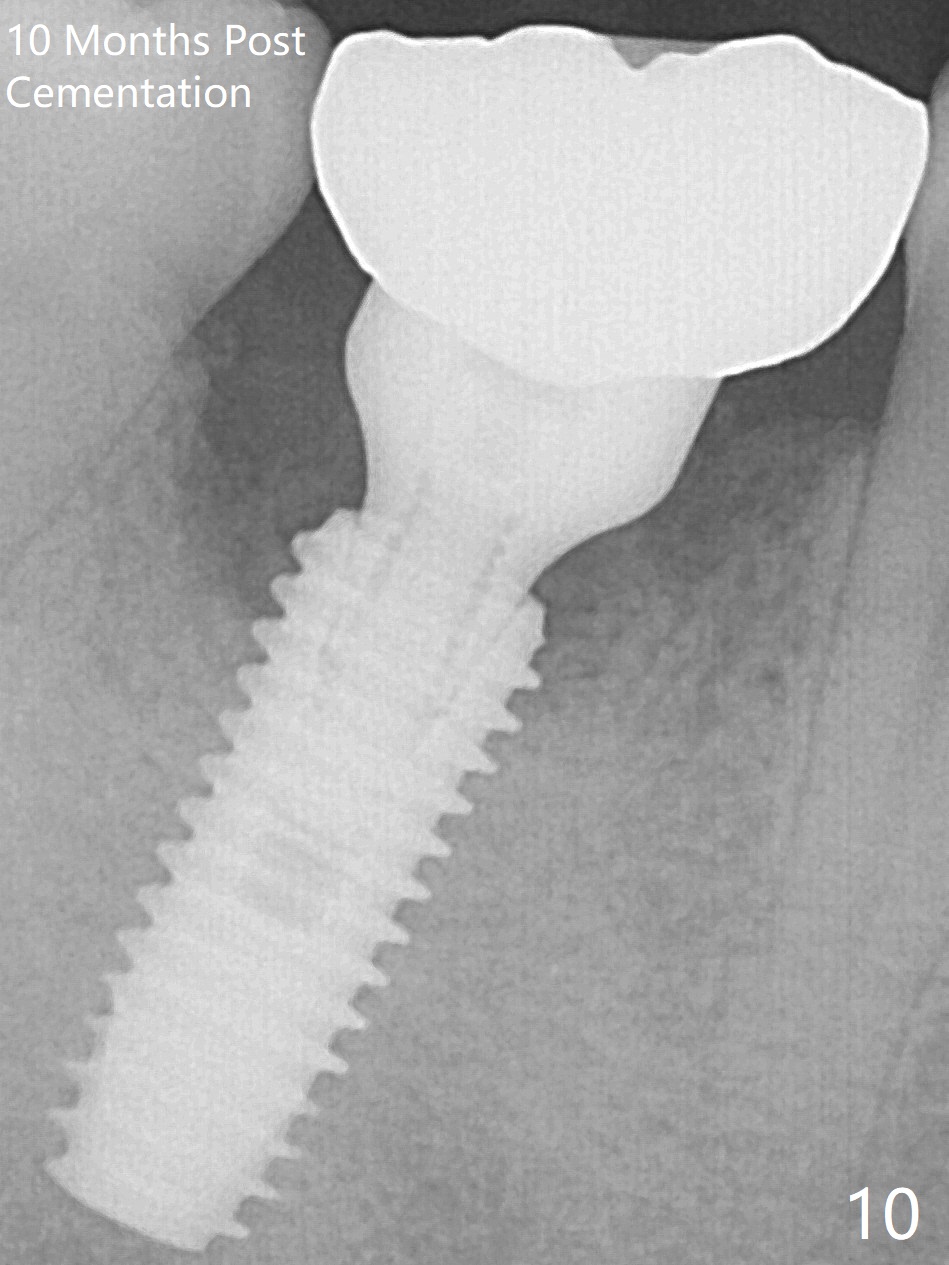

Fortunately no paresthesia is reported postop. Why is the Inferior Alveolar Canal not violated? Fig.7 is a coronal section of CBCT taken for a 40-year-old man at the lower 1st molar (at the septum). At the region, the Canal (brown circle) is close to the lingual plate (L). Because of severe bone loss of the lingual plate of this case (Fig.8 *), osteotomy is intentionally created buccal (green). The deep osteotomy may not contact the Canal, while the hemorrhage may stem from the medullary space (M in Fig.4,7). Bone morphology at the coronal end of the implant apparently changes 4 months postop, suggesting osteointegration (Fig.9). Impression is taken. Bone density around the implant at the crest seems to increase (Fig.10), while there is no soft tissue deficiency 10 months post cementation (Fig.11). The bone appears to regenerate toward the abutment, particularly distally, 14.5 months post cementation (Fig.12). Periimplantitis develops (bleeding on water pik and erythematous and tender buccal gingiva) 1 year 7 months post cementation (Fig.13,14). The 1st three threads are exposed (*). Bone graft with PRF and 6-month membrane or Cytoplast will be needed. Pain disappears 3 days of oral antibiotic. The gingiva looks healthy 1 month later when he returns for bone graft (Fig.15). But the lingual gingival cuff is not so healthy when the crown/abutment is removed (Fig.16 <). Bone graft is not done. For those patients with suboptimal oral hygiene, implants should be placed as low as possible, better with guide for precision.